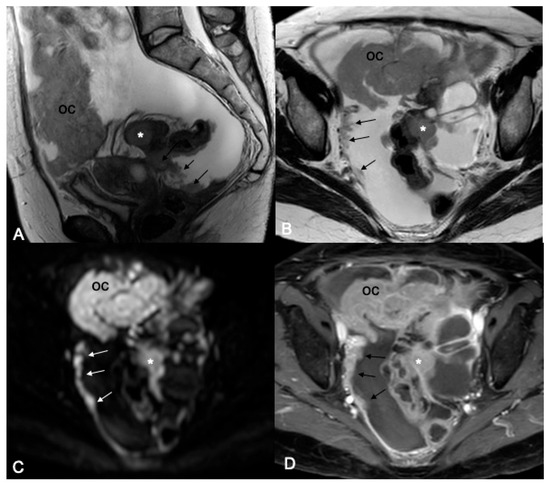

Figure 1